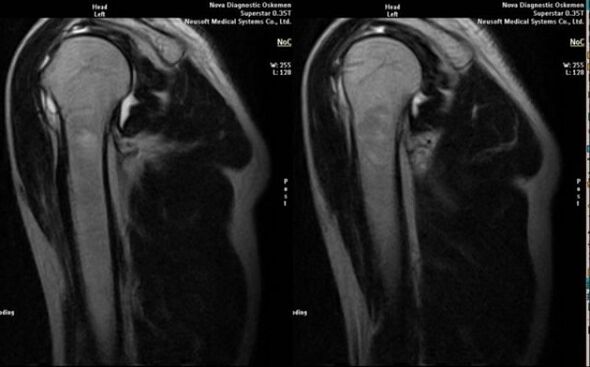

- μαγνητικός συντονισμός και αξονική τομογραφία.

Τα σημάδια που υποδεικνύουν άμεσα την ανάπτυξη αρθρώσεως περιλαμβάνουν την εμφάνιση σημαντικής στένωσης του διαστήματος της άρθρωσης, σκλήρυνση των υποχόνδρινων δομών, λέπτυνση της ίδιας της στιβάδας των χονδροκυττάρων, εμφάνιση οστεοφύτων και εναπόθεση κρυστάλλων άλατος στο ενδοαρθρικό υγρό.